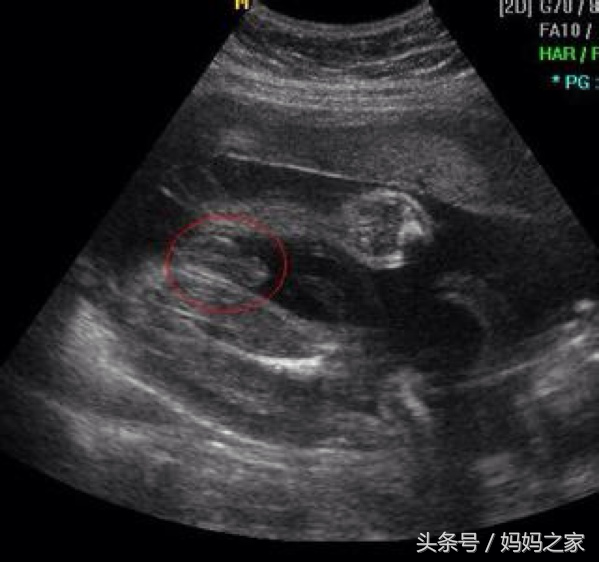

四个月的时候我去医院做B超,结果显示是儿子,怕一次不准,六个月的时候再去照的时候就确定了是儿子了,如今生下来了果然是个儿子,婆婆高兴的心情是掩盖不住的,老人家嘛,抱孙子都是特别开心的。